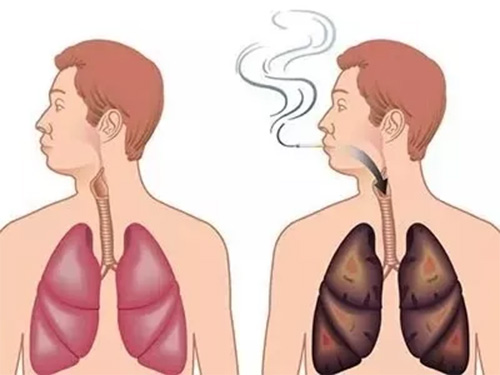

肺癌 喉癌 甲状腺癌 都有一相同症状 嘴里有这种变化要当心 健康

肺癌 喉癌 甲状腺癌 都有同一个症状 嘴里出现这种变化要小心 网易订阅

不仅抽烟能引起咽喉癌 Hpv也能引起咽喉癌 香港九龙hpv预约